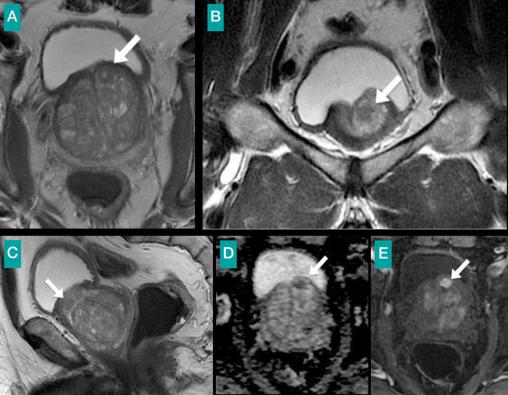

Patient de 63 ans ayant une élévation du PSA à 16 ng/mL.Le toucher rectal ne trouve qu'une grosse prostate souple. Deux séries de biopsies prostatiques sont négatives. Imagerie par résonance magnétique de détection pour ciblage de nouvelles biopsies. Les séquences pondérées en T2 en axial (A), coronal (B) et sagittal (C) mettent en évidence une hypertrophie prostatique et petite lésion en hyposignal au niveau de la prostate antéro-supérieure. (D) La cartographie ADC montre une restriction de la diffusion. (E) La séquence dynamique avec injection (30 s) montre un rehaussement intense et précoce de la lésion. La biopsie ciblée trouve un adénocarcinome de prostate de score de Gleason 7.